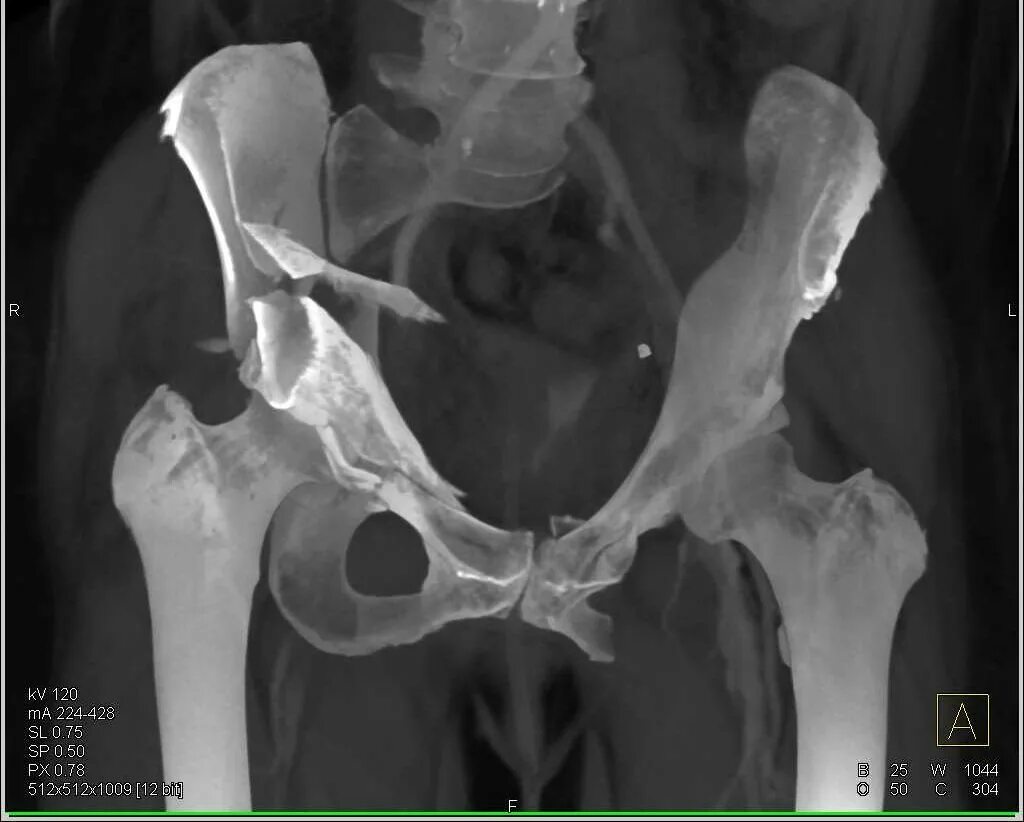

Перелом гребня